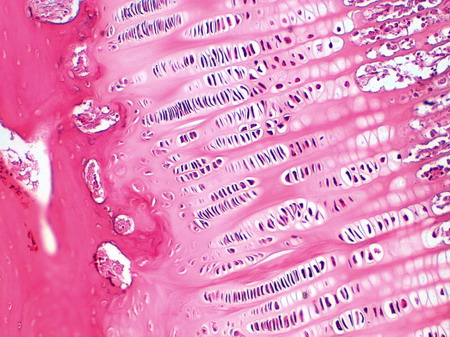

| IB-7 Miocardio (Hematoxilina Férrica) |

Visión general: sección de pared de miocardio teñida con hematoxilina férrica que nos permite visualizar mejor la estriación típica del musculo estriado cardíaco.

Visión específica: si buscamos un área en la que veamos el recorrido de los miocardiocitos siguiendo su eje mayor, observaremos la alternancia de bandas claras y oscuras. Las diferencias con respecto al músculo estriado esquelético radican en que en este caso los núcleos son únicos y ocupan la porción central del citoplasma. Se observan como espacios muy claros con cromatina laxa y con uno o dos puntos oscuros correspondientes al nucléolo. Además las células no transcurren una junto a la otra pero independientes como ocurría en el músculo esquelético, sino que se anastomosan mediante uniones específicas de carácter escaleriforme que se conocen como discos intercalares. Se reconocen como bandas de color negro que, en algunos puntos, cruzan perpendicularmente a la célula. Obsérvese como entre célula y célula discurren capilares con eritrocitos en su interior formando como pilas de moneda.